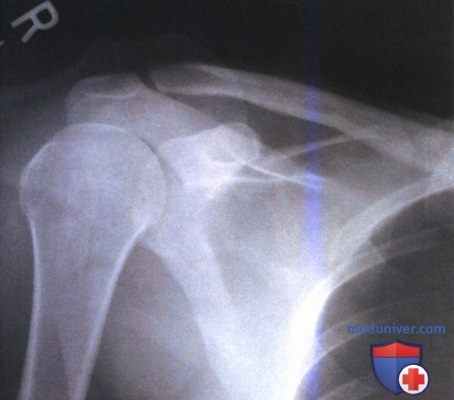

РИСУНОК 14 Компьютерная рентгенография правого плечевого сустава в ПЗ проекции. На изображении выявляется артефакт—фантомное изображение.

• Представляет собой артефакт, который возникает при неадекватной очистке запоминающей пластины перед последующей экспозицией. После экспозиции запоминающую пластину помещают в считывающее устройство, где она сканируется красным лазером, а затем направляется в блок очистки, где под воздействием высокоинтенсивного света происходит высвобождение запасенной на ней энергии. Блок очистки способен стереть запоминающую пластину, если величина ее экспозиции превышает нормальную не более чем в пять раз. При большей величине экспозиции запасенная энергия останется на запоминающей пластине в виде фантомного изображения, вследствие чего последующая экспозиция и сканирование приведут к получению изображения, похожего на таковое при двойной экспозиции (рис. 14)